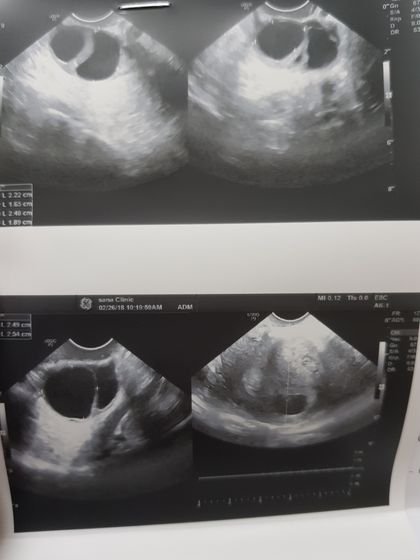

Всем привет. Сходила на узи иииии… 6.5 недель сердцебиение +, плод в матке. Все ничего но сказали есть 3 кисты в правом яйчнике. У меня никогда такого не было. Даже не представляю что это такое. Ну и все кто знает про меня у меня стоит стент в мочеточечнике который из за маленького срока не могут убрать. Сижу жду врача уролога. Будут обсуждать когда можно убрать. Кстати не поиму на фото где там эмбриончик.